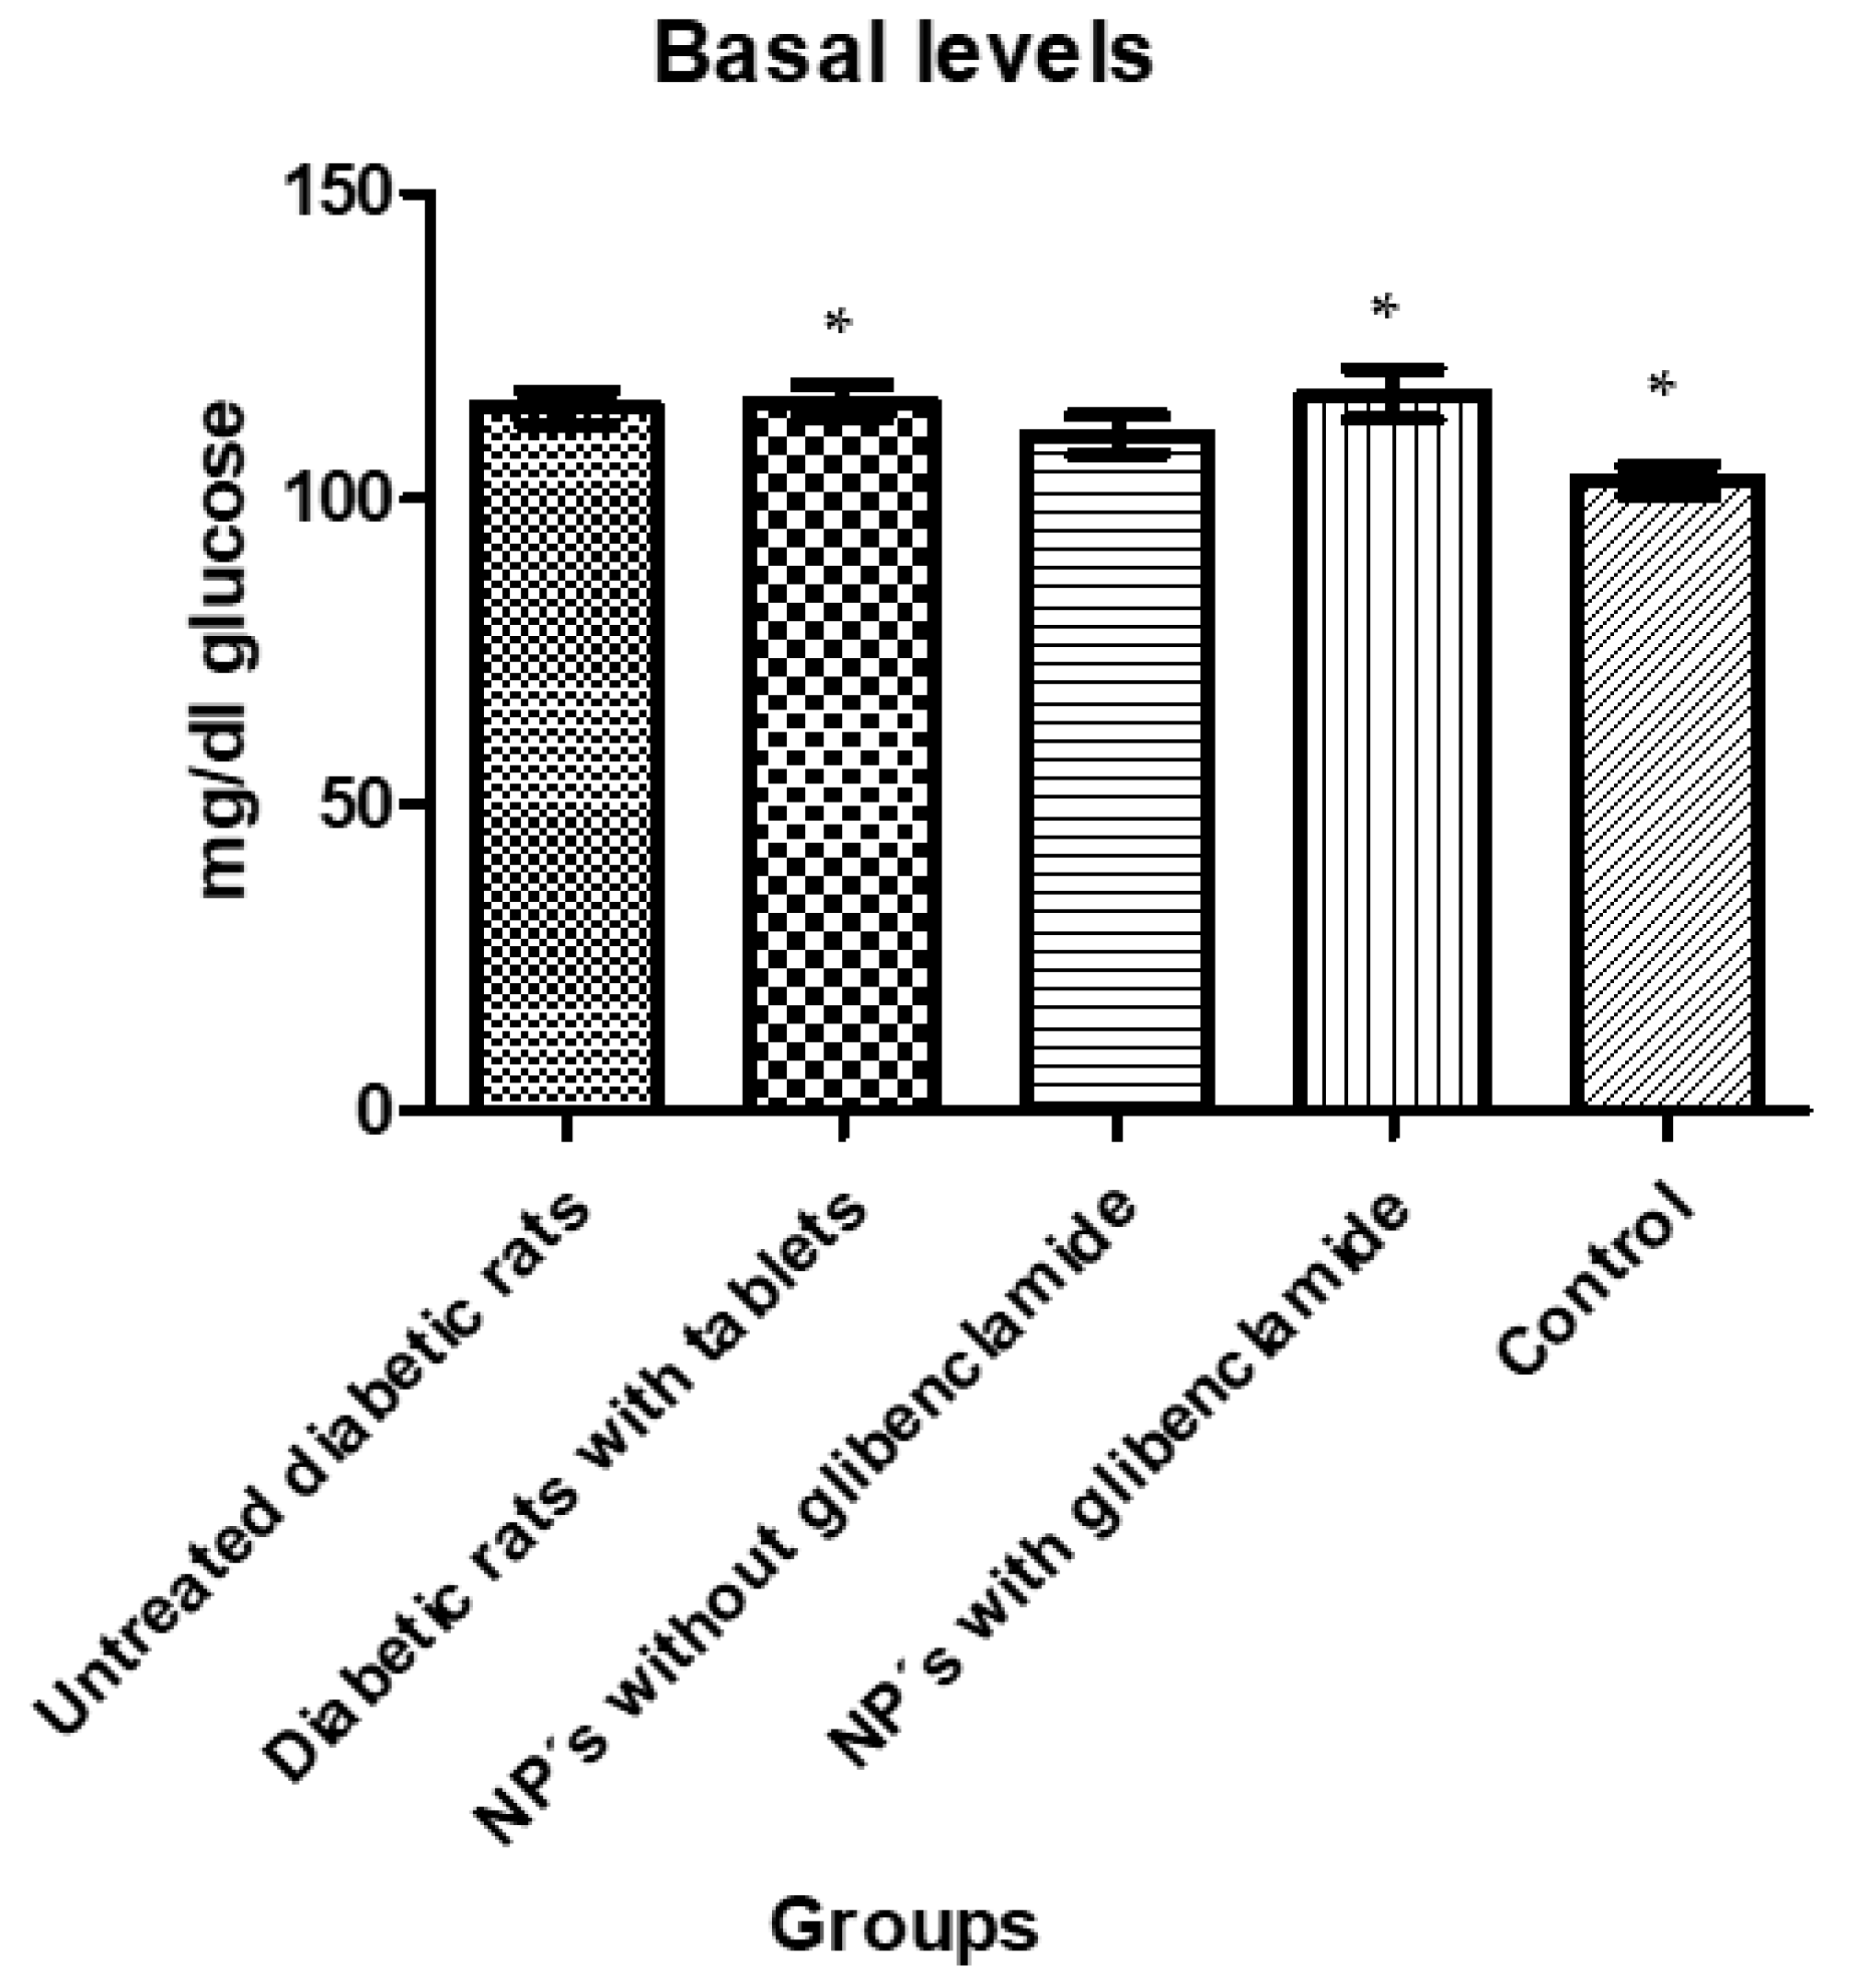

3.1.7. In Vivo Tests

| Animals Were Divided into 5 Different Groups with 5 Individuals Each as Follows: |

|---|

| Group 1: untreated diabetic rats |

| Group 2: diabetic rats with conventional pharmaceutical form (tablets) |

| Group 3: diabetic rats administered with NP without glibenclamide |

| Group 4: diabetic rats administered with NP with glibenclamide |

| Group 5: control |

| Tukey’s Multiple Comparison Test | Significant p < 0.05 | Summary | 95% CI of diff |

|---|---|---|---|

| Group 1 vs. Group 2 | No | ns | −13.78 to 12.00 |

| Group 1 vs. Group 3 | No | ns | −8.380 to 17.40 |

| Group 1 vs. Group 4 | No | ns | −15.03 to 10.75 |

| Group 1 vs. Group 5 | No | ns | −0.9797 to 24.80 |

| Group 2 vs. Group 3 | No | ns | −6.755 to 17.55 |

| Group 2 vs. Group 4 | No | ns | −13.40 to 10.90 |

| Group 2 vs. Group 5 | Yes | * | 0.6451 to 24.95 |

| Group 3 vs. Group 4 | No | ns | −18.80 to 5.505 |

| Group 3 vs. Group 5 | No | ns | −4.755 to 19.55 |

| Group 4 vs. Group 5 | Yes | * | 1.895 to 26.20 |